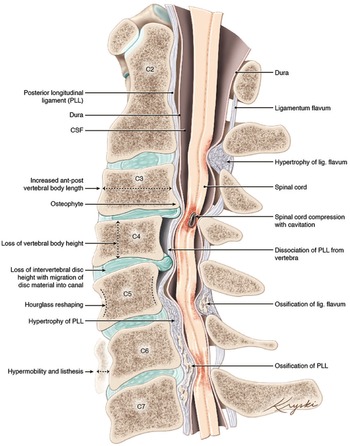

DCM represents an overarching clinicopathological entity encompassing a variety of age-related and genetically associated degenerative conditions of the cervical spinal column including degenerative disc disease (DDD), cervical spondylotic myelopathy (CSM), and ligamentous aberrations including ossification of the posterior longitudinal ligament (OPLL), (Figure 1). Reference Nouri, Tetreault and Singh4 On occasion, congenital disorders including Klippel-Feil Syndrome(KFS) and Ehlers-Danlos syndrome may contribute to the development of DCM. Reference Nouri, Tetreault and Singh4 These eventually culminate in chronic compression of the spinal cord causing neurological compromise through static and dynamic injury mechanisms. In this section, we will outline the clinical entities surrounding the term DCM as well as provide an overview on the pathophysiological mechanisms of chronic spinal cord compression encountered in DCM.

Figure 1: An illustration of the varied anatomical changes in the cervical spine that may underly the development of degenerative cervical myelopathy. Medical illustration by Diana Kryski (Kryski Biomedia). Reprinted with permission from Nouri A, Tetreault L, Singh A, et al. Degenerative Cervical Myelopathy: Epidemiology, Genetics, and Pathogenesis. Spine 2015;40:E675.